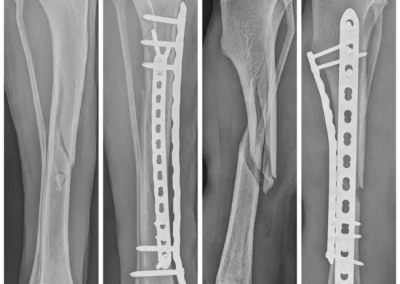

- Traumatología y ortopedia: diagnóstico y cirugía de fracturas, displasia o problemas articulares.